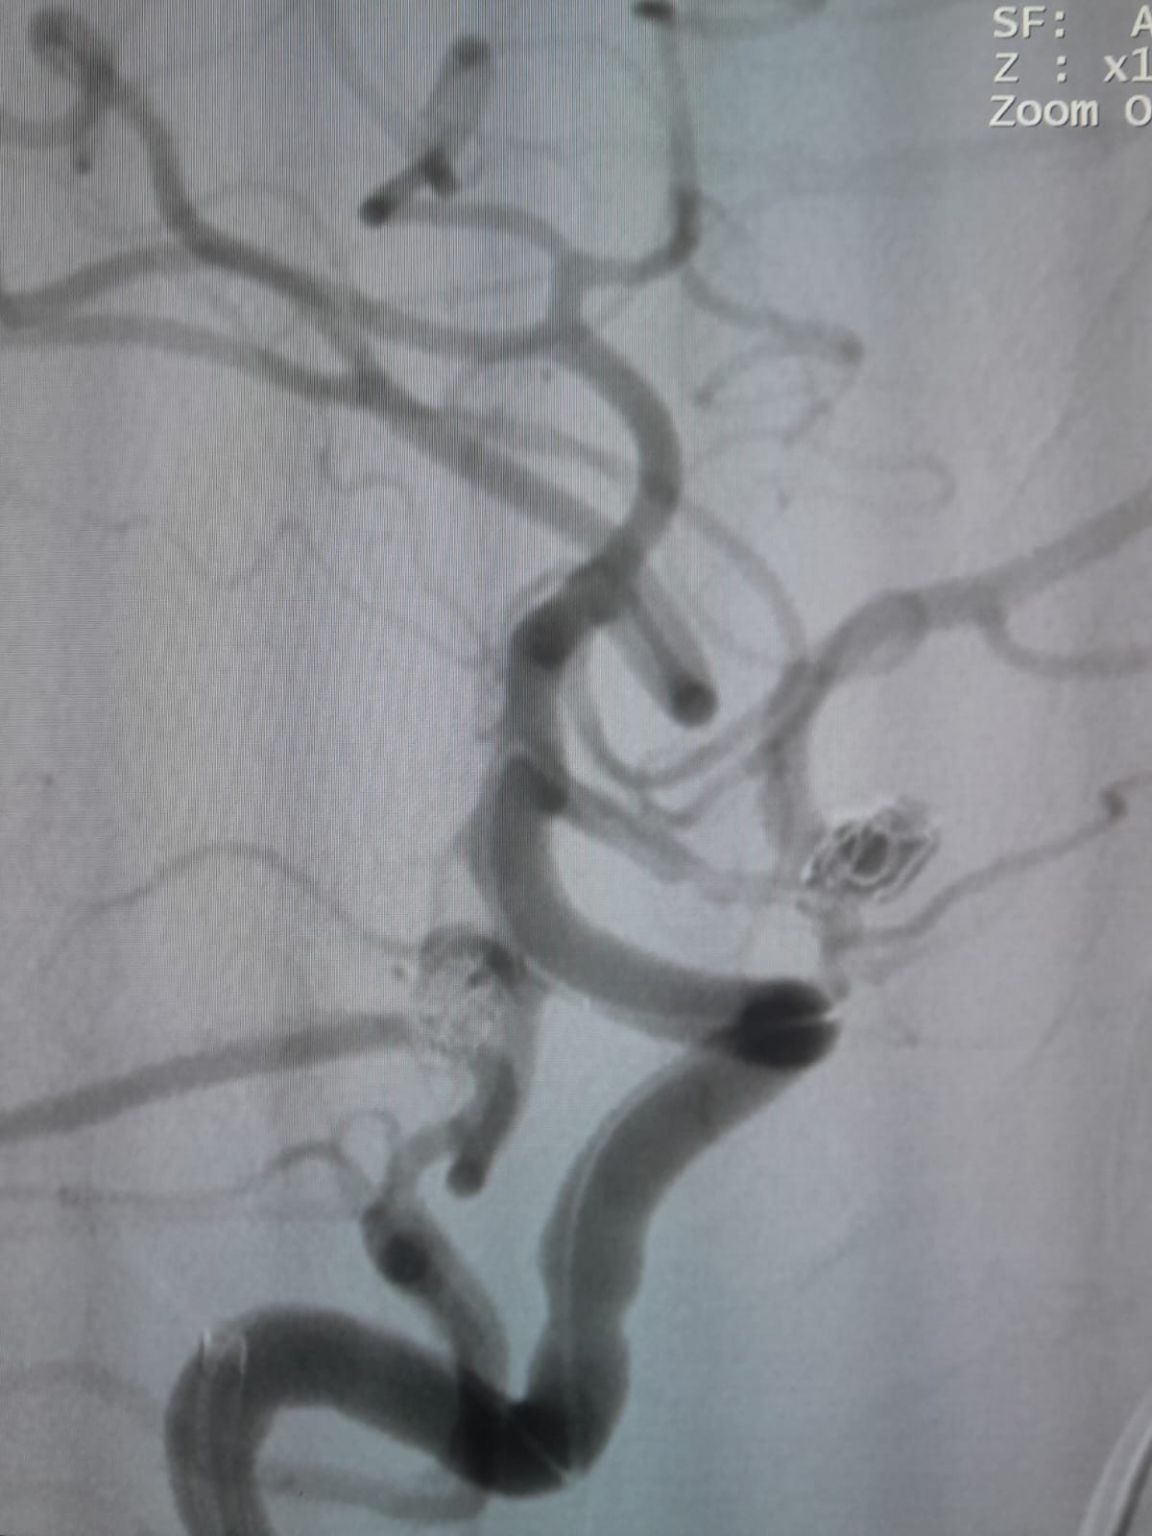

El paciente fue diagnosticado con un aneurisma de la arteria comunicante anterior (AComA) recién descubierto y un aneurisma de la arteria comunicante posterior (PComA) que había sido tratado previamente con embolización con espiral. Las imágenes de seguimiento revelaron un relleno residual en el aneurisma PComA, que requirió una intervención adicional.

Aneurisma de la arteria comunicante posterior (re-tratamiento)

Durante el seguimiento, se observó llenado residual en el aneurisma de la arteria comunicante posterior tratado previamente. El equipo reingresó al sitio usando el sistema de acceso a través de la aplicación de la tarjeta de crédito®Microcatéter desechable (TJMC18 Plus) e implementado con éxito un Nuva®Desviador del flujo (TJED-D-4.5-16), que demostró aposición ideal de la pared y desviación excelente del flujo, llevando a los resultados altamente satisfactorios del tratamiento.